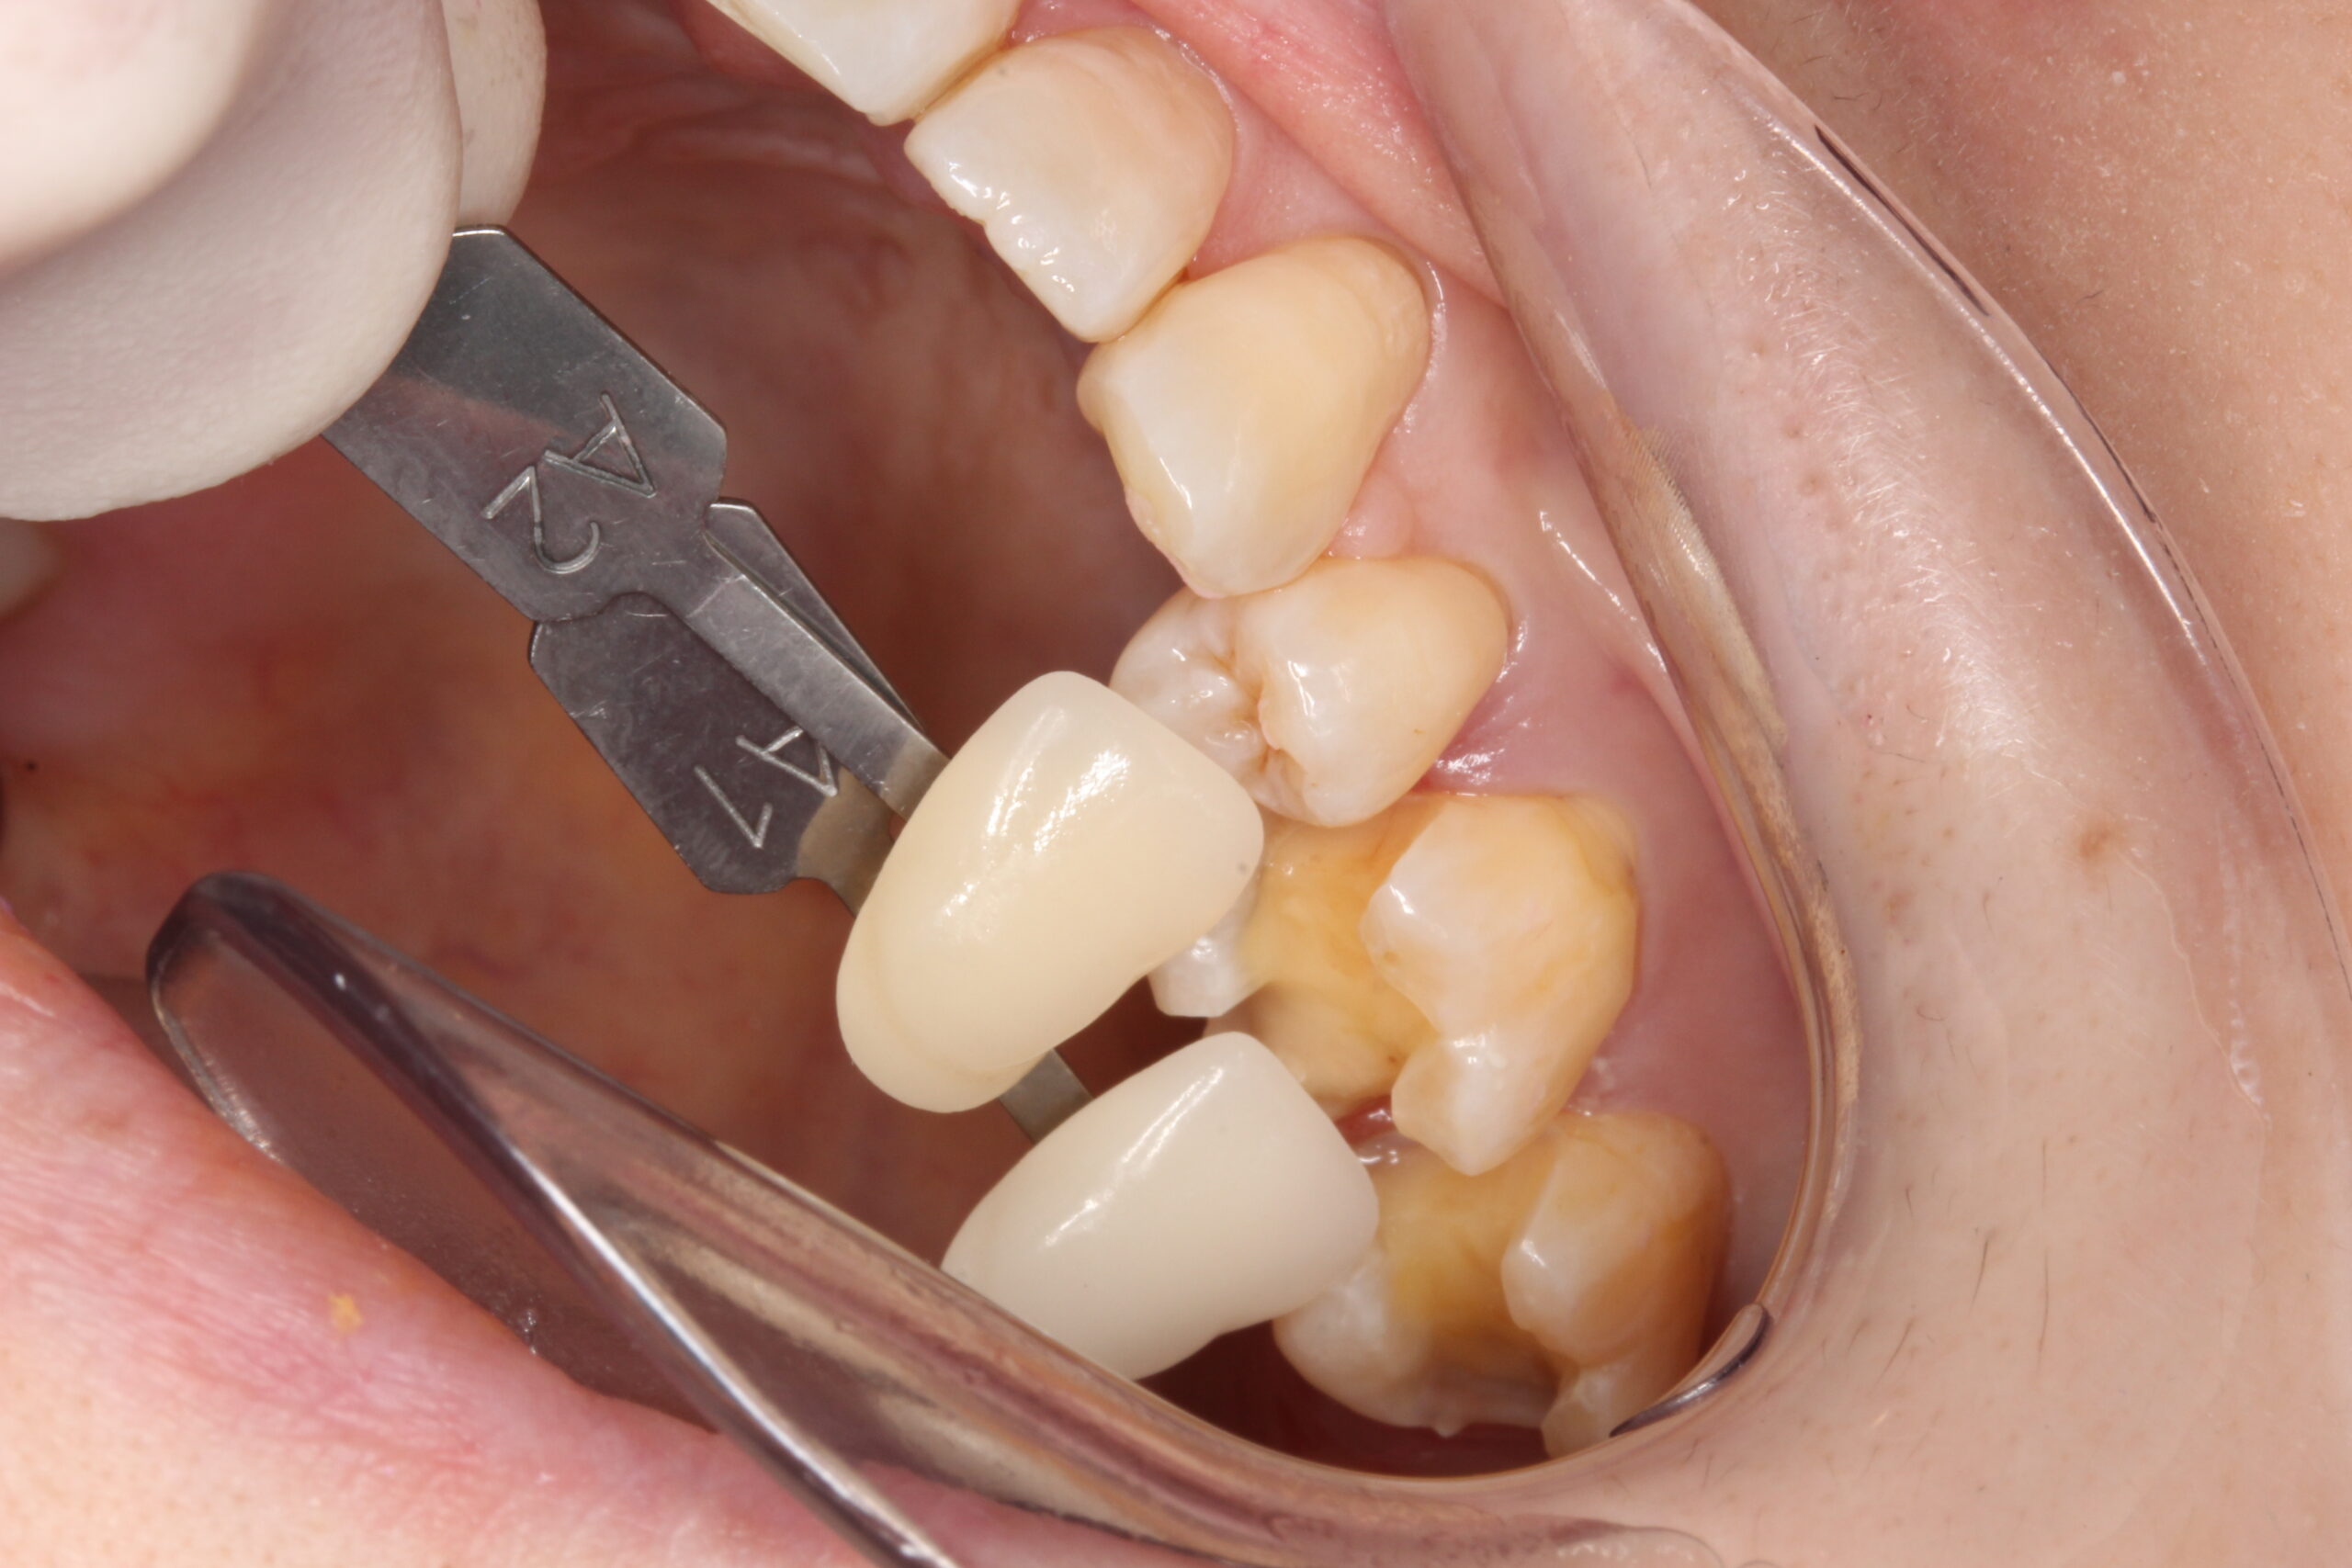

フロスが引っかかる浮いて合っていないジルコニアインレーをセラミックに交換

• Before

After